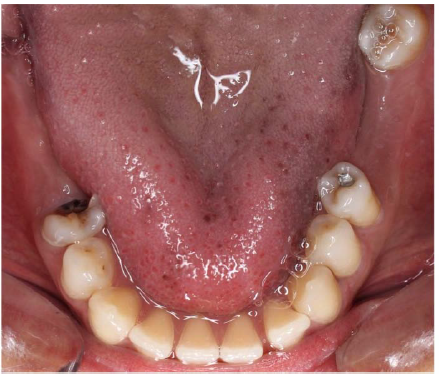

The patient underwent radiological examination. The panoramic views revealed the enlargement of marrow spaces with widened trabeculae in both the maxilla and mandible (Figure 2). The soft tissue drapes had normal color and contours. The only abnormal finding in soft tissue examination was macroglossia (Figure 4).

Figure 4. Macroglossia in a thalassemic patient.